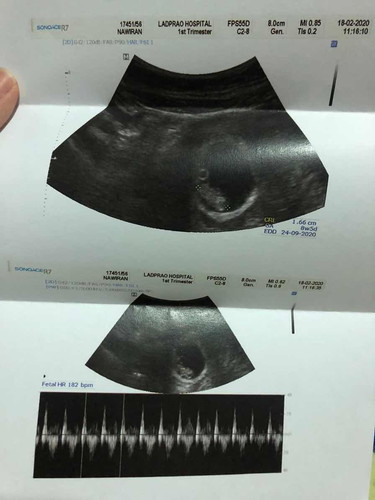

18/02/2020 ฝากครั้ง+อัตตาร้าซาวด์ เช็คอายุครรภ์และขนาดของbaby พร้อมเลือกแพ็กเกจของรพ. Baby 8w ขนาด 1.66 (ท้องแรกค่ะ)